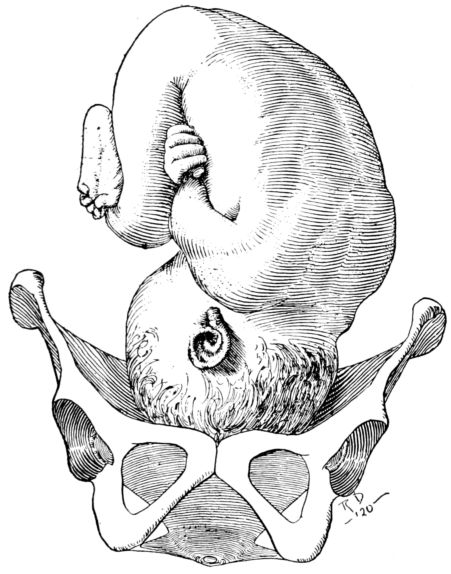

The true pelvis, on the other hand, is of greatest possible obstetrical importance since the child must pass through its narrow passage during birth. It lies below and somewhat behind the inlet; is an irregularly shaped, bottomless basin, and contains the generative organs, rectum and bladder. Its bony walls are more complete than those of the false pelvis, and are formed by the sacrum, coccyx and innominate bones. Its lower margin constitutes the outlet, or inferior strait, and being longer in its antero-posterior dimension than in its transverse measurement, its long axis is at right angles to the long axis of the inlet. (Fig. 3.) A baby’s head, accordingly, must twist or rotate in making its descent through this bony canal, for the long diameter of the head must first conform to one of the long diameters of the inlet, either transverse or oblique, and then turn so that the length 24of the head is lying antero-posteriorly, in conformity to the long diameter of the outlet, through which it next passes.

Thus it becomes apparent that the structure of the pelvis requires the child’s head, not only to rotate in its passage through the birth canal, but also to describe an arc, since the part of the head which passes down the posterior wall travels farther in a given time than the part which passes under the pubis.